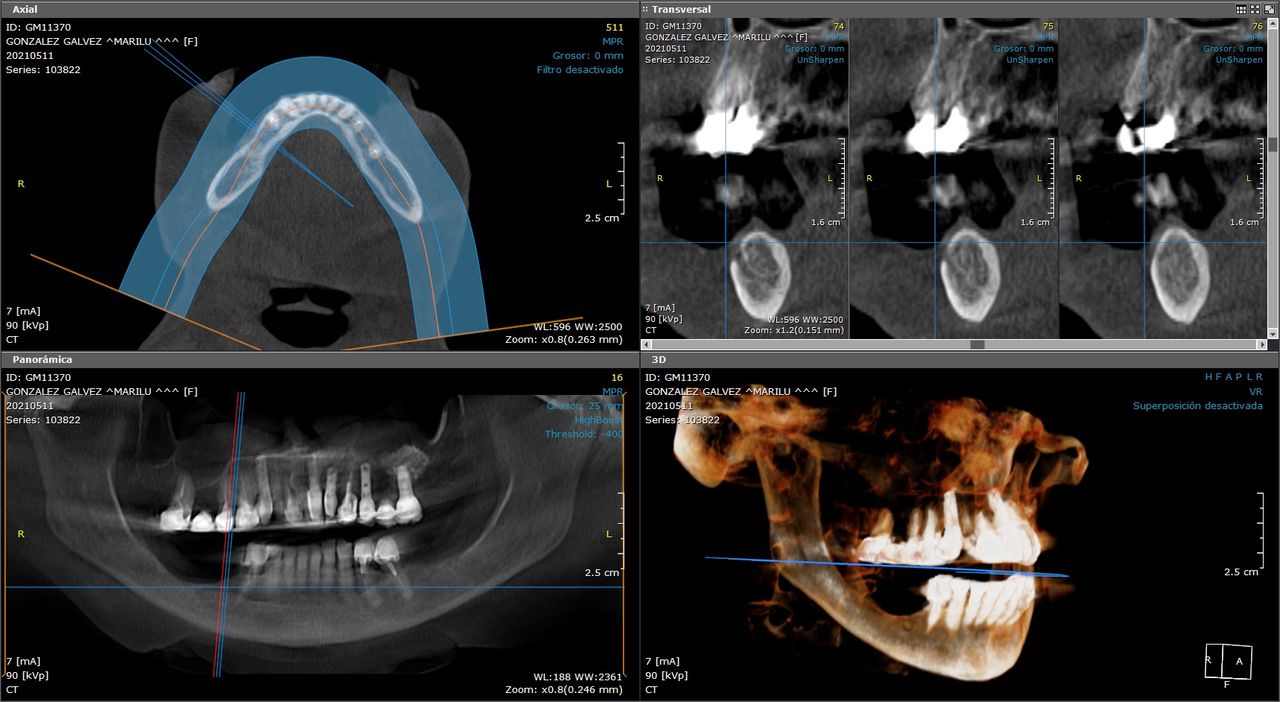

Diagnóstico por imagen

Le recomendamos realizar un estudio mas extenso llamado cone beam para ver el grado de afectación, le sugerimos acudir a una consulta para valorar su caso. Quedamos a sus órdenes.